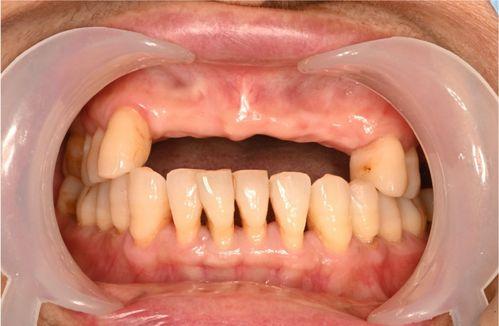

前牙區(qū)牙齒缺失